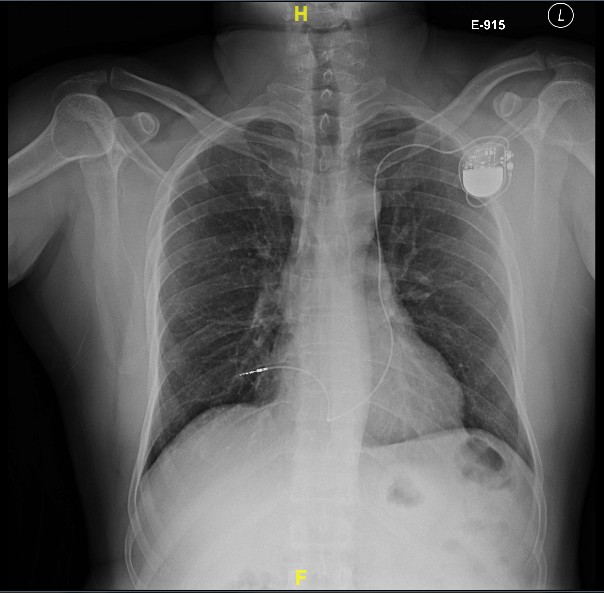

Post implant

Post procedure care

• Immobilisation / bed rest ?

• Analgesia

• Chest X ray after 4-6 hours

• ECG / Pacemaker check